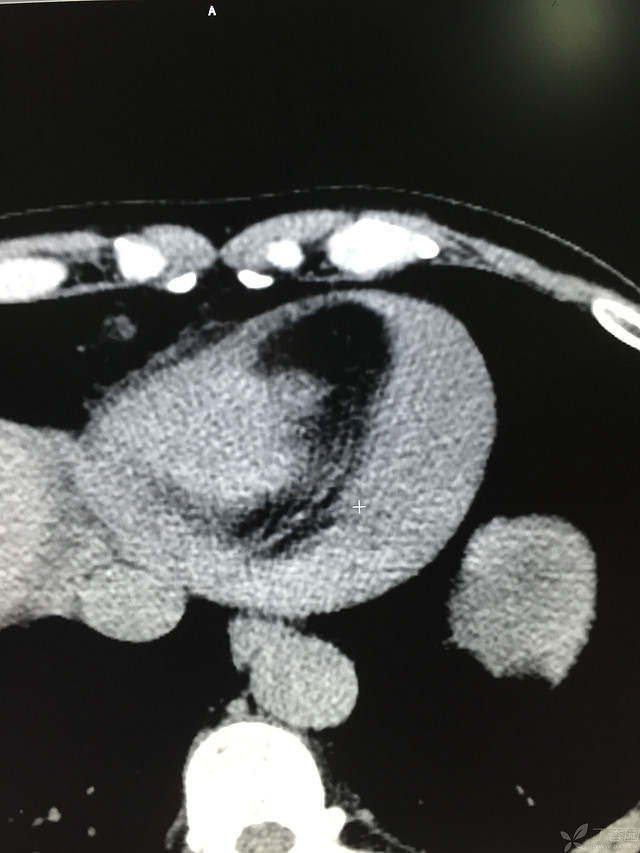

患者性别:男

患者年龄:64岁

简要病史:三天前休息时突发胸前区疼痛伴大汗,到当地医院输液治疗后缓解,3小时前情绪激动后再次出现胸痛伴大汗,胸部压迫感,持续不缓解入院,到当地医院测血压180/?mmHg泵入硝酸甘油转入我院。

体格检查:血压94/72mmHg(右侧)96/74mmHg(左侧),心率78此/分,其他未见阳性体征